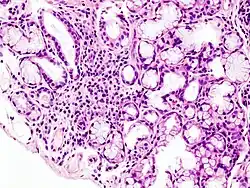

| Image with a microscope of focal lymphoid infiltration in the minor salivary gland associated with Sjögren's disease | |